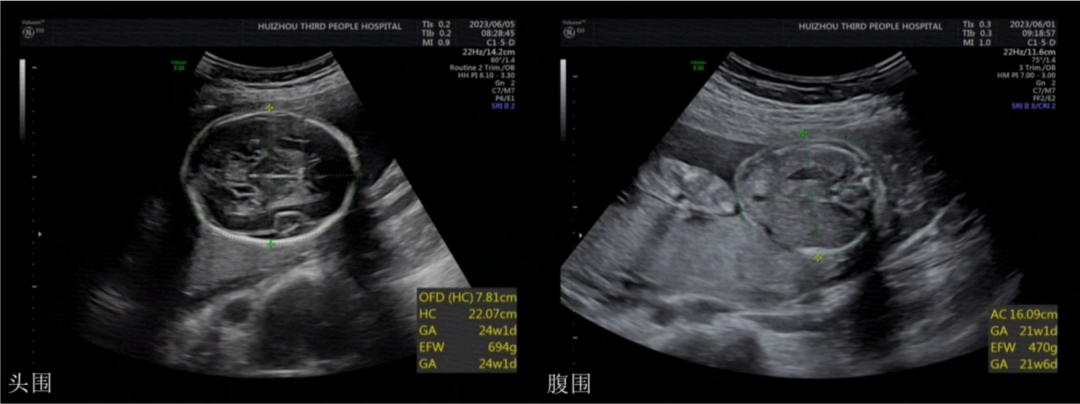

頭圍和腹圍

頭圍指環(huán)頭一周的長度,24-28周頭圍參考值220-258mm,腹圍指肚子一周的長度,也叫腹部周長。

胎兒腹圍標準(cm)

24周: 18.74±2.23

25周: 19.64±2.20

26周: 21.62±2.30

27周: 21.81±2.12

28周: 22.86±2.41